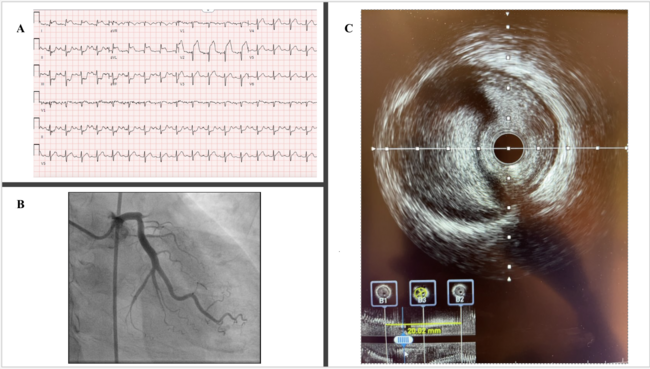

A 54-year-old man presented following a motor vehicle crash that resulted in a subarachnoid hemorrhage (SAH). Electrocardiogram showed anterolateral ST-segment elevations (Figure A). Troponin I was elevated at 3.19 ng/mL, and echocardiogram showed an antero-apical wall-motion abnormality with an ejection fraction of 20% to 25% (Video 1). Anticoagulation and dual antiplatelet therapy for acute coronary syndrome (ACS) were initially withheld given concern for SAH expansion. However, within 8 hours, troponin I rose to 87.20 ng/mL.

After discussion with the neurosurgical team, mono-platelet therapy with 81 mg of aspirin was initiated, and cardiac catheterization was performed via the right femoral artery. Angiography revealed an occluded ostial left anterior descending artery (LAD) (Figure B, Video 2). Given these findings, the patient was given 7000 units of unfractionated heparin and loaded with 600 mg of clopidogrel. The lesion was readily crossed with a wire and dilated with a compliant balloon, restoring Thrombosis in Myocardial Infarction-2 flow and revealing a 95% ostial-to-proximal LAD diffuse stenosis (Video 3). Intravascular ultrasound imaging demonstrated compression of the vessel lumen by an intramural hematoma, confirming a traumatic dissection (Figure C, Video 4). A cutting balloon was used to fenestrate the false lumen. Flow improved but remained suboptimal angiographically; thus, a single drug-eluting stent was deployed (Video 5). Dual-antiplatelet therapy (DAPT) with the addition of 75 mg of clopidogrel daily was started, with no further neurologic sequelae. Post-procedure echocardiogram showed a persistently reduced ejection fraction of 25% to 30%. Guideline-directed medical therapy (GDMT) was initiated, and the patient was discharged home with DAPT for 1 year followed by aspirin monotherapy thereafter. At follow-up in the cardiology clinic, the patient had been tolerating GDMT well and denied experiencing any subsequent angina.